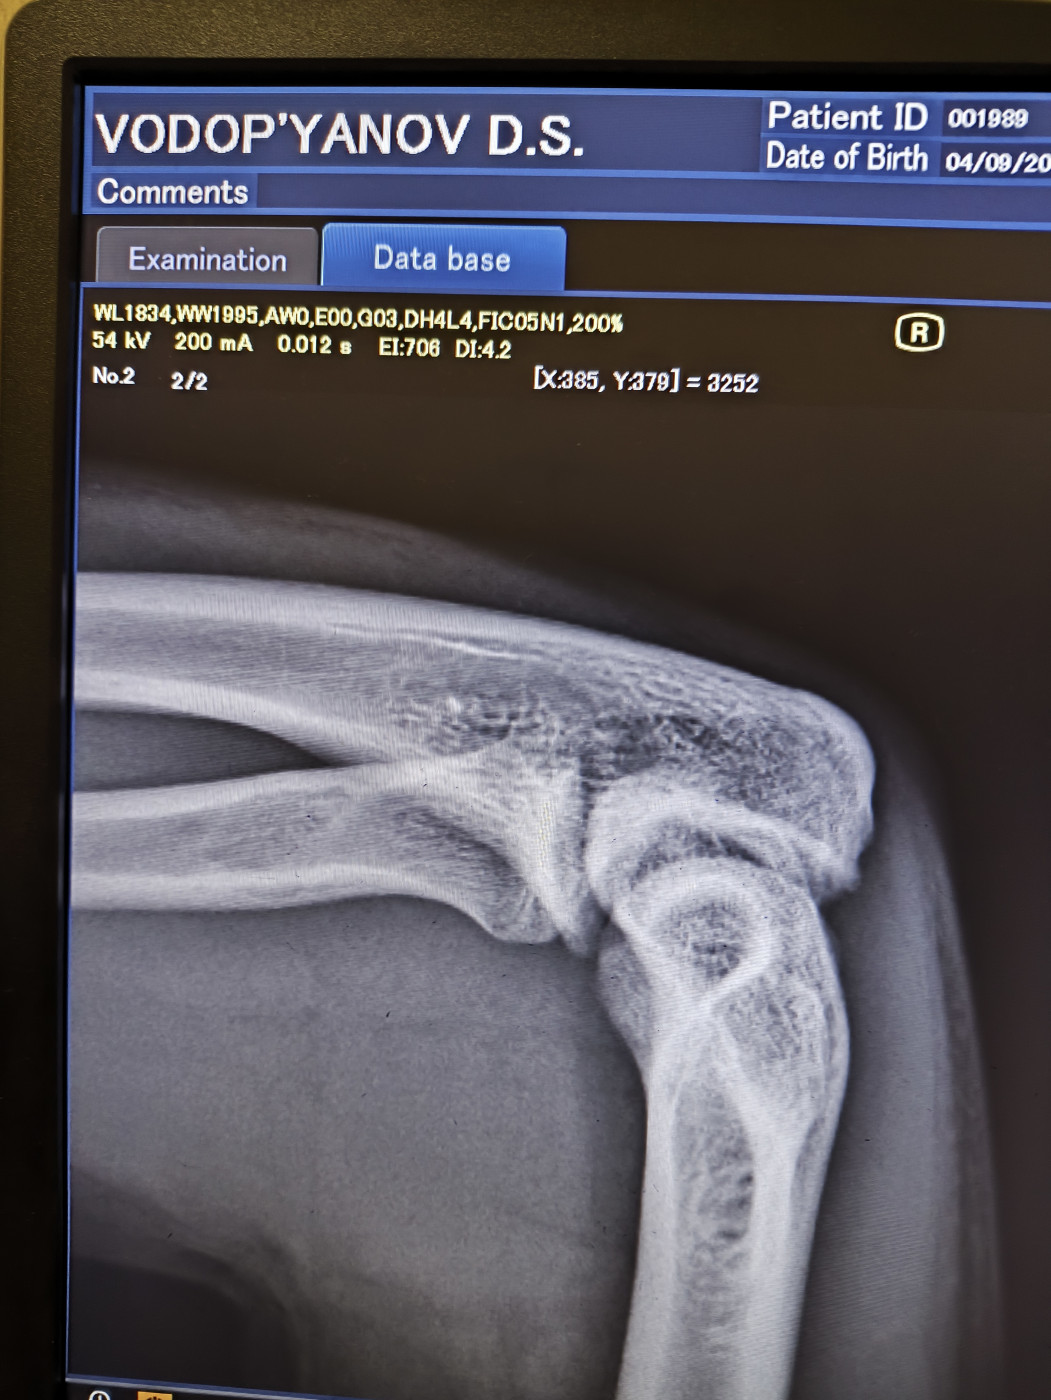

Боролся вчера на руках во время борьбы резкий хруст и не смог разгибать руку хотя при этом пальцы шевелятся, поехал в больницу и сказали что отломился кусочек кости, наложили гипс. Вопрос можно ли обойтись в данном случае только гипсом без операции,?